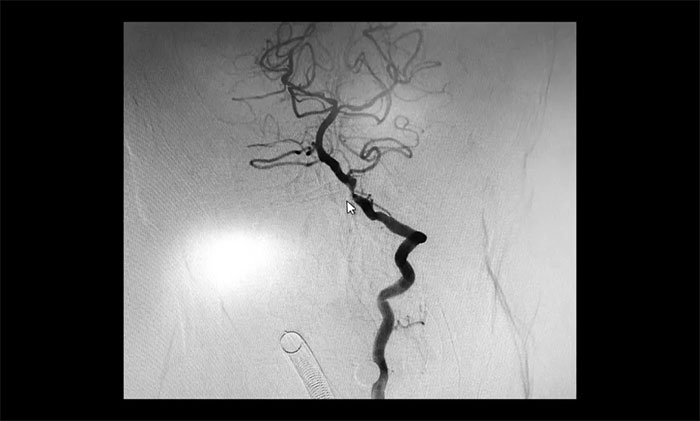

术后康复观察一月余,于耀宇主任团队再次为曹老伯行右侧颈动脉支架置入及左侧椎动脉支架置入手术。术中造影显示,右侧颈内动脉起始段重度狭窄,狭窄长度8mm左右。左侧椎动脉 V4 段重度狭窄,长度6mm左右。运用娴熟扎实的技术,在充分做好脑保护的前提下经过多次球囊扩张后,顺利释放支架于狭窄处。造影提示支架打开良好,血管狭窄基本恢复正常,支架贴壁佳,支架内血流通畅,远端血流良好。

▲ 术后,右侧颈内动脉及左侧椎动脉狭窄明显改善